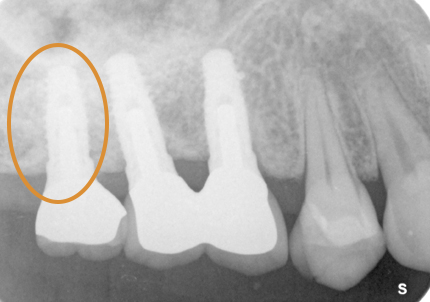

1.初診時口腔内(2007年7月31日)

主訴 ①:左下痛くて歯肉が腫れる

左下7番部ポケット7~9ミリ

左下5番部ポケット3~5ミリ

治療計画 ①:歯周病初期治療、歯周外科

2.再生療法:エムドゲイン(2008年3月)

骨欠損部にエムドゲイン、バイオスを填入して、メンブレンにて閉鎖縫合する